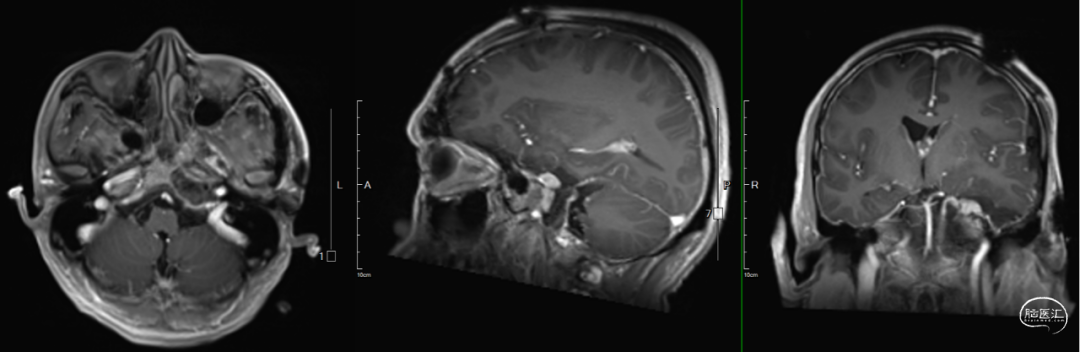

术后影像学资料

橙色箭头:离断颧弓还纳

红色箭头:脂肪填塞封堵

黄色箭头:人工硬膜重建

术后影像学提示:病灶切除彻底,脂肪+人工硬膜封堵Meckel’s腔在位。